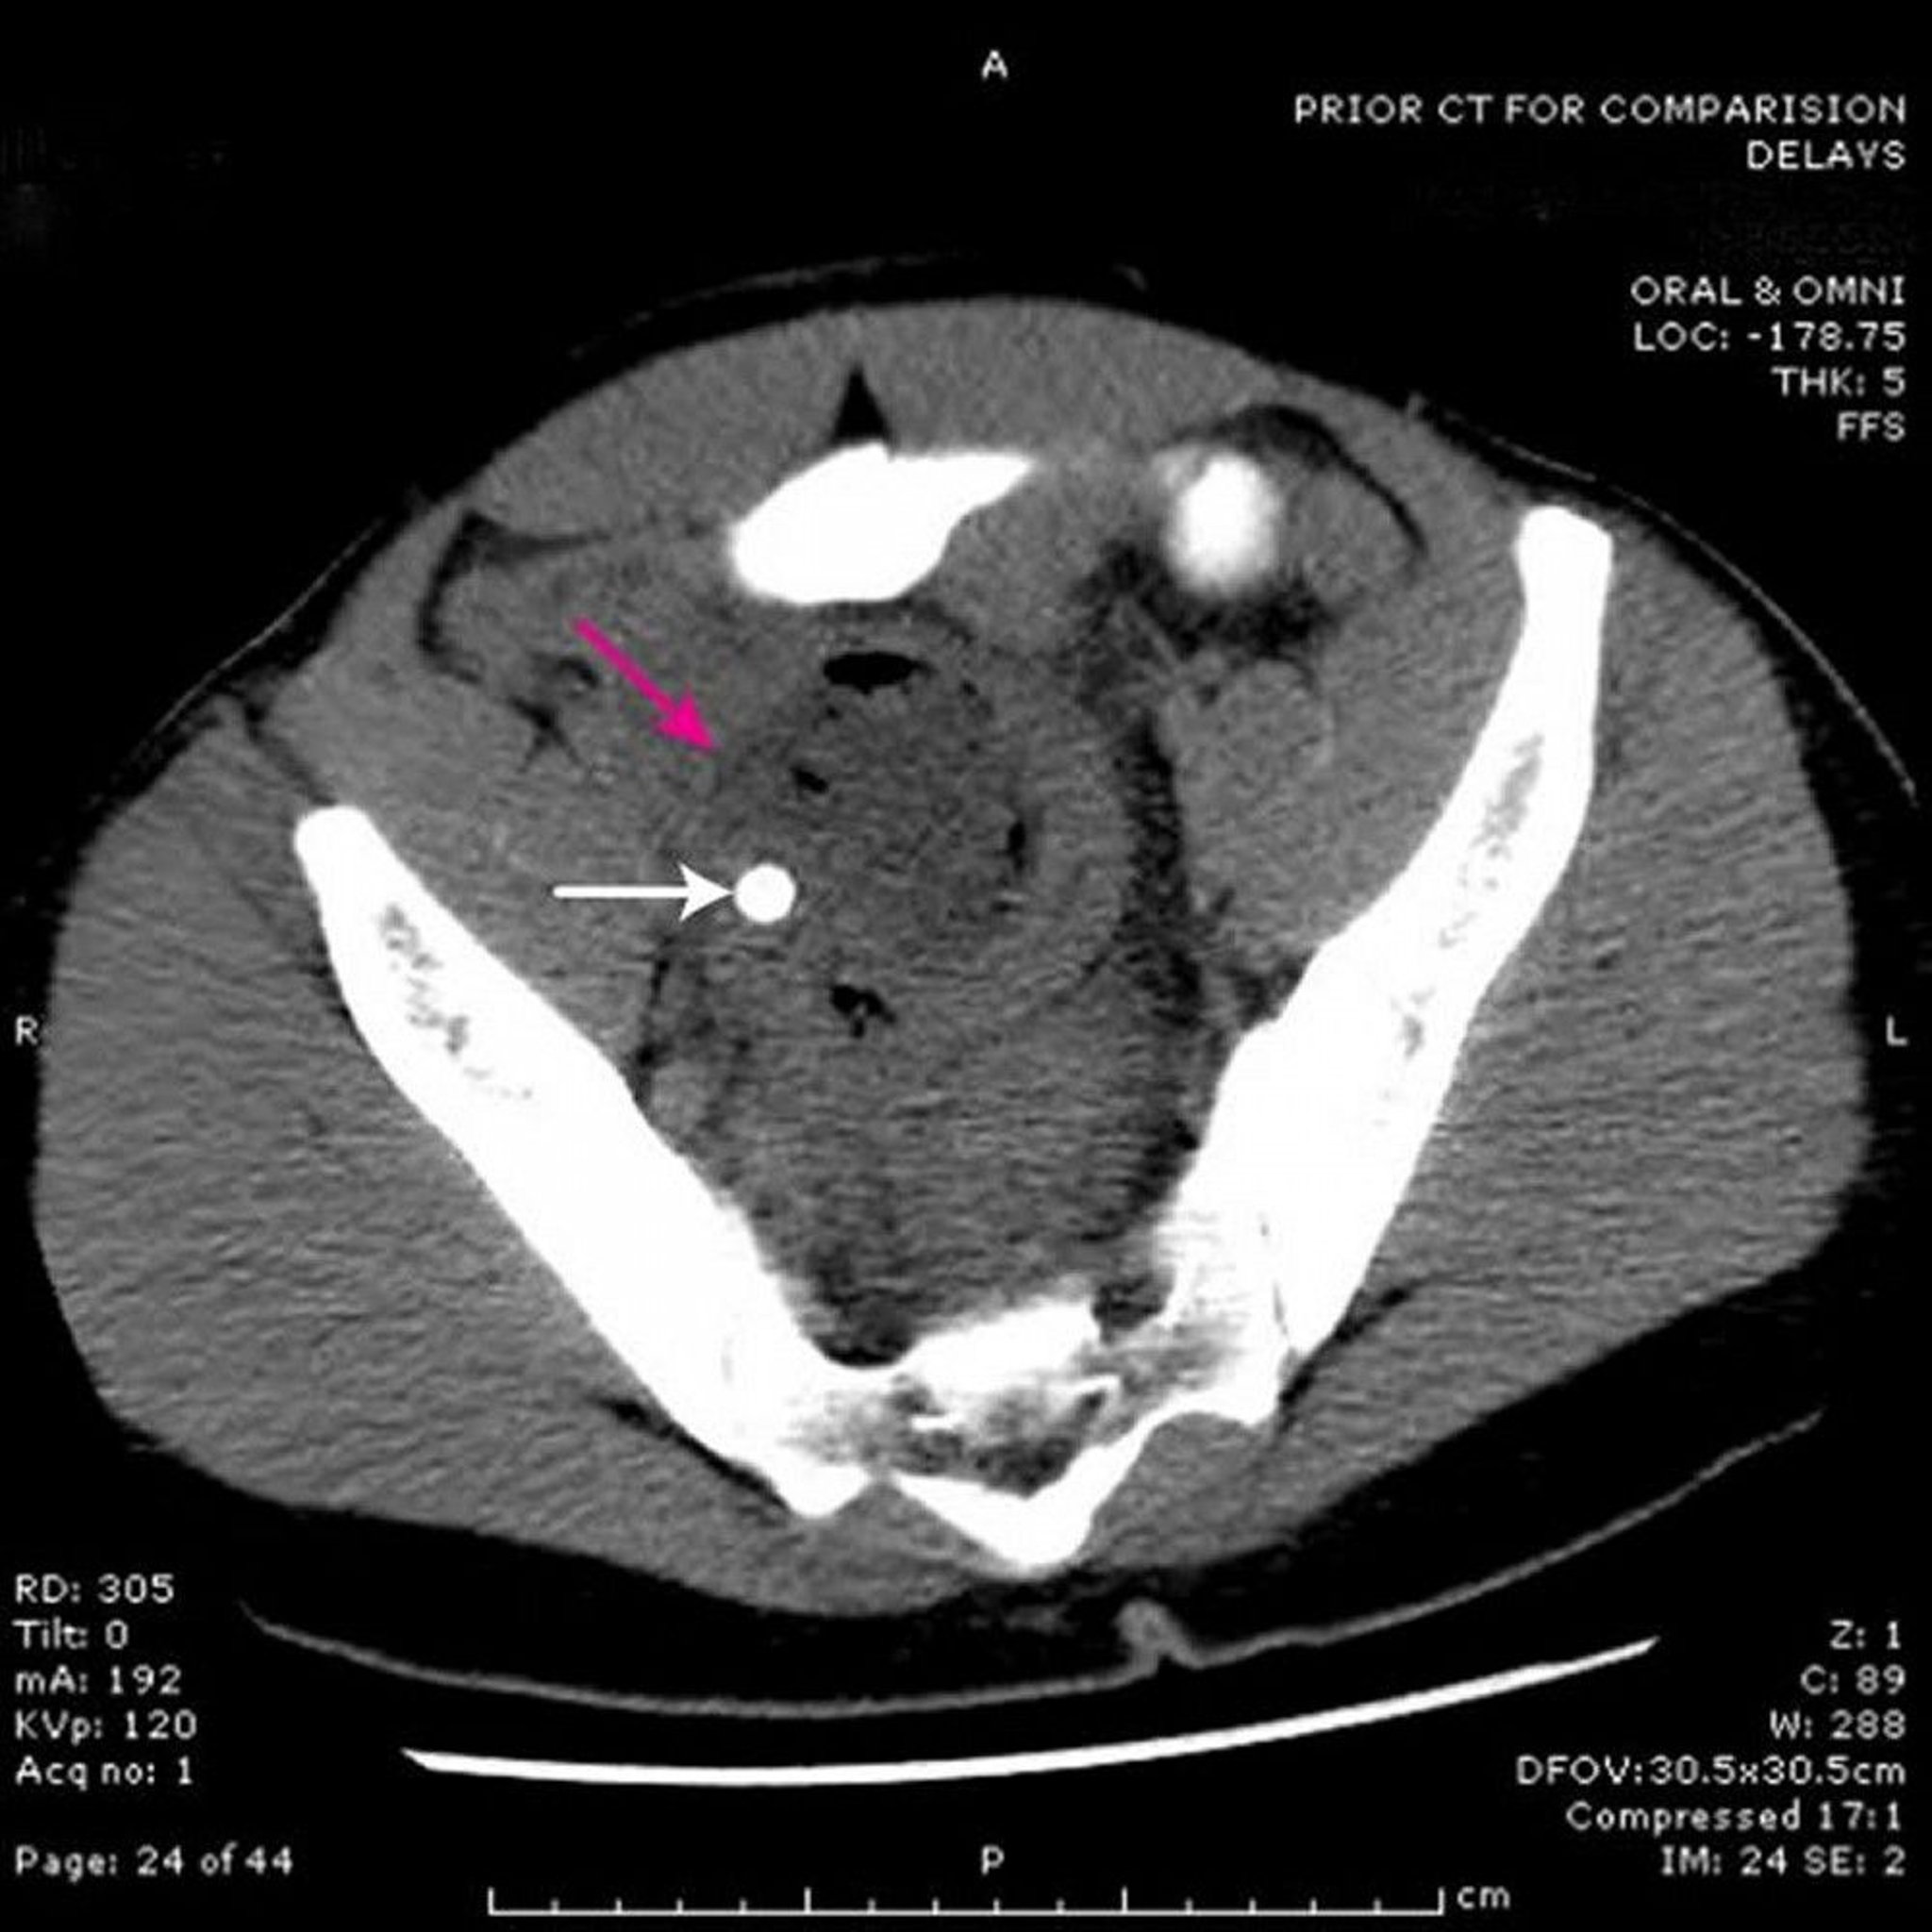

Pelvic Abscess (CT Scan)

This CT scan shows an abscess (red arrow) in the pelvis caused by appendicitis. Note the radio-opaque fecalith (white arrow).

Image provided by Parswa Ansari, MD.